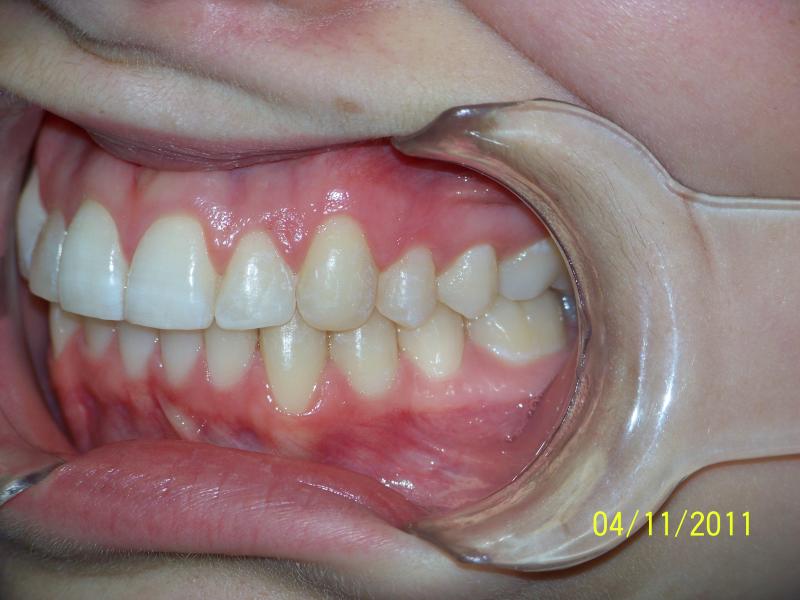

INVISALIGN, 10 months, 1 series of aligners to correct alignment, deep overbite and shift teeth to the right to match upper and lower mid line, TOTAL TREATMENT TIME: 10 months COSMETIC DENTISTRY: incisal reduction of anterior teeth before and after Invisalign.

Deep Overbite, Teeth Reshaping, Testimonial